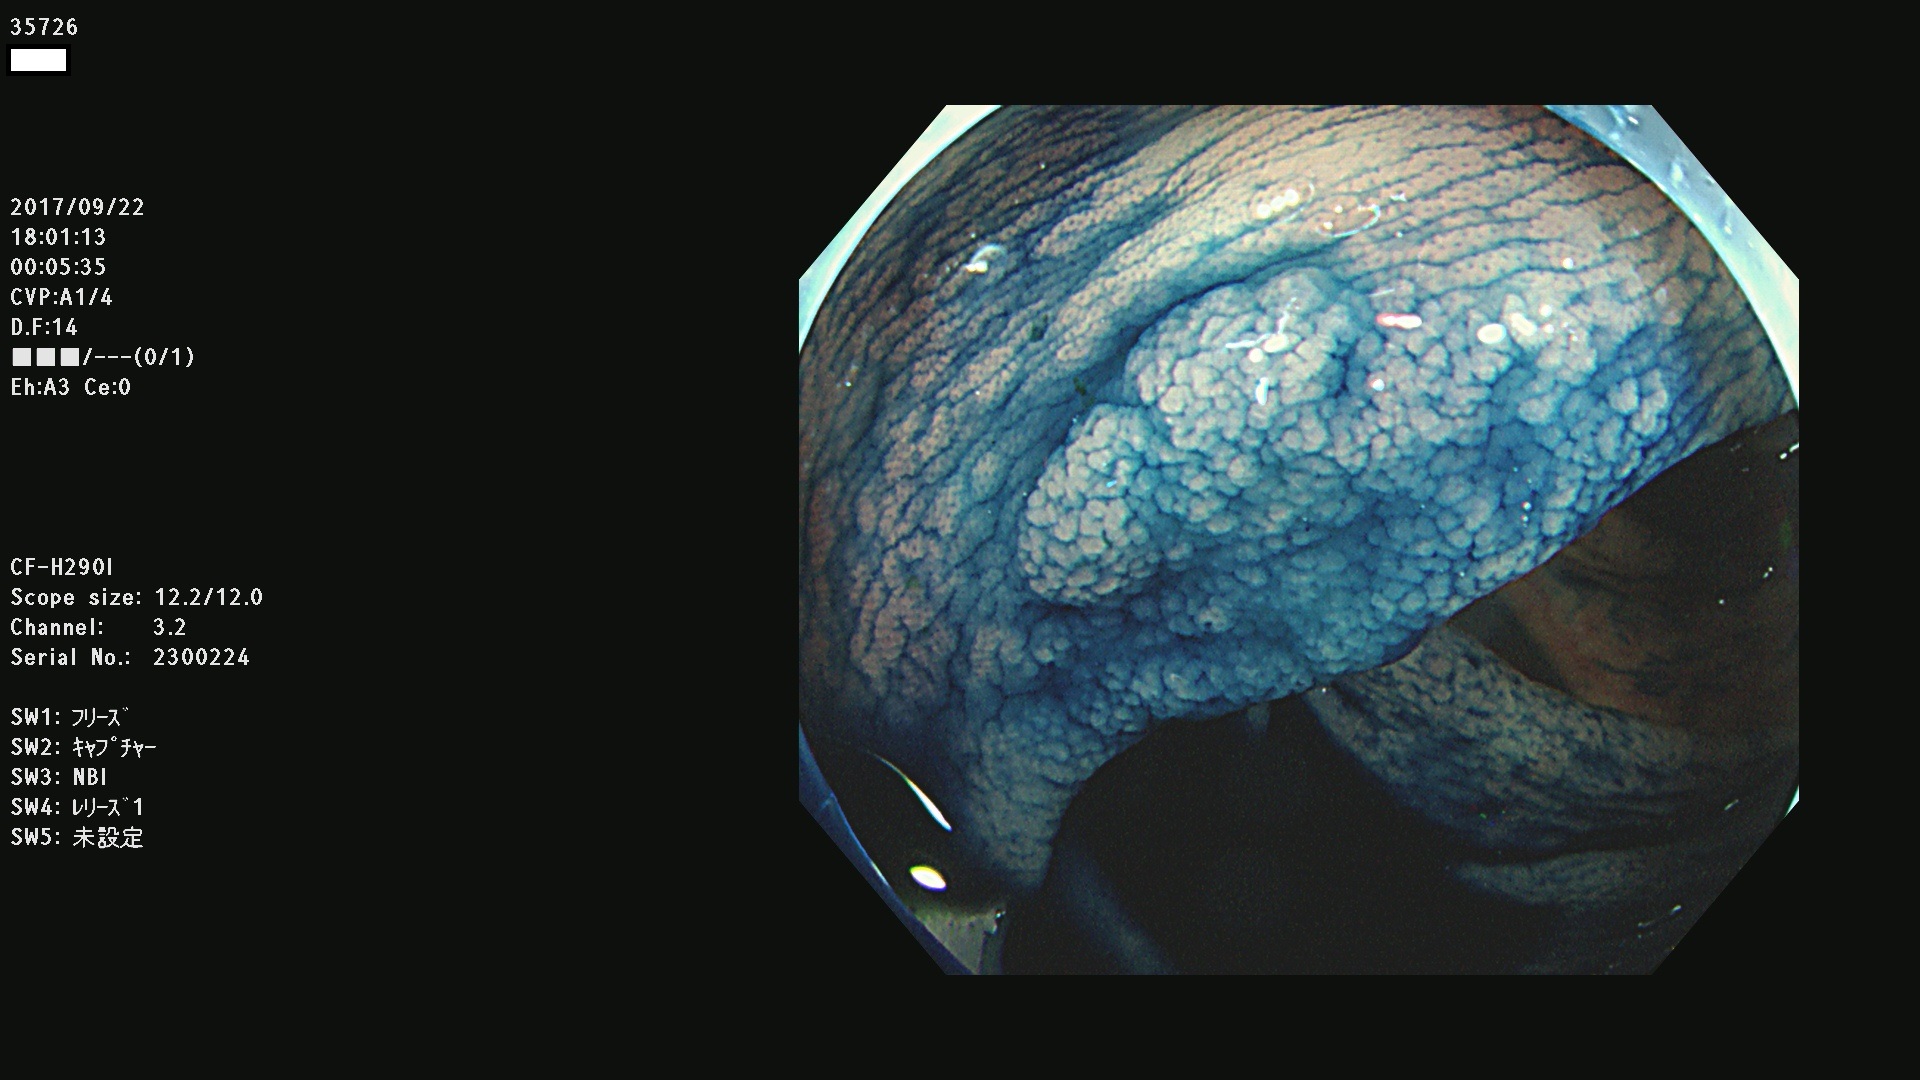

発見困難で危険性の高い平坦型病変(上記100名より抽出)